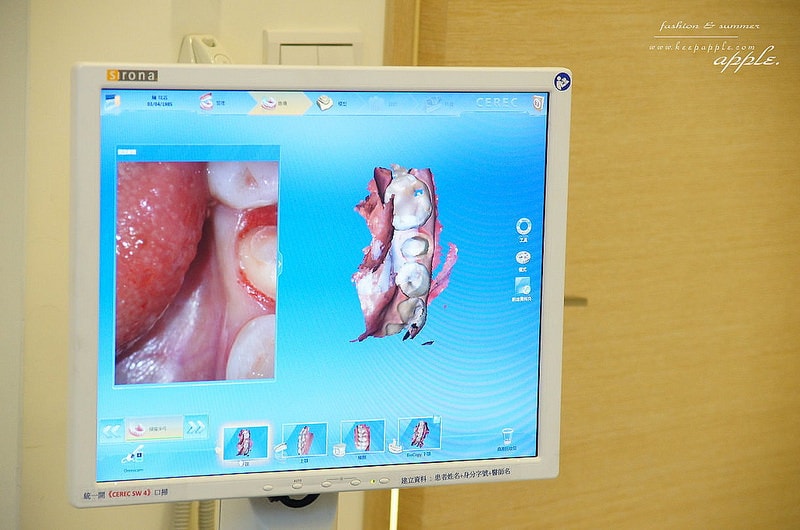

就是用超厲害的數位化口內掃瞄機進行掃描啦!

持續掃描大約三到五分鐘的時間

就可以把整個口腔的牙齒及牙肉組合成3D影像

居然還可以360度翻轉喔!

這台機器真的很厲害,甚至很多大醫院都還沒有引進

這顆就是要裝牙套的牙齒

會先像這樣磨成小小的

等一下好裝牙套